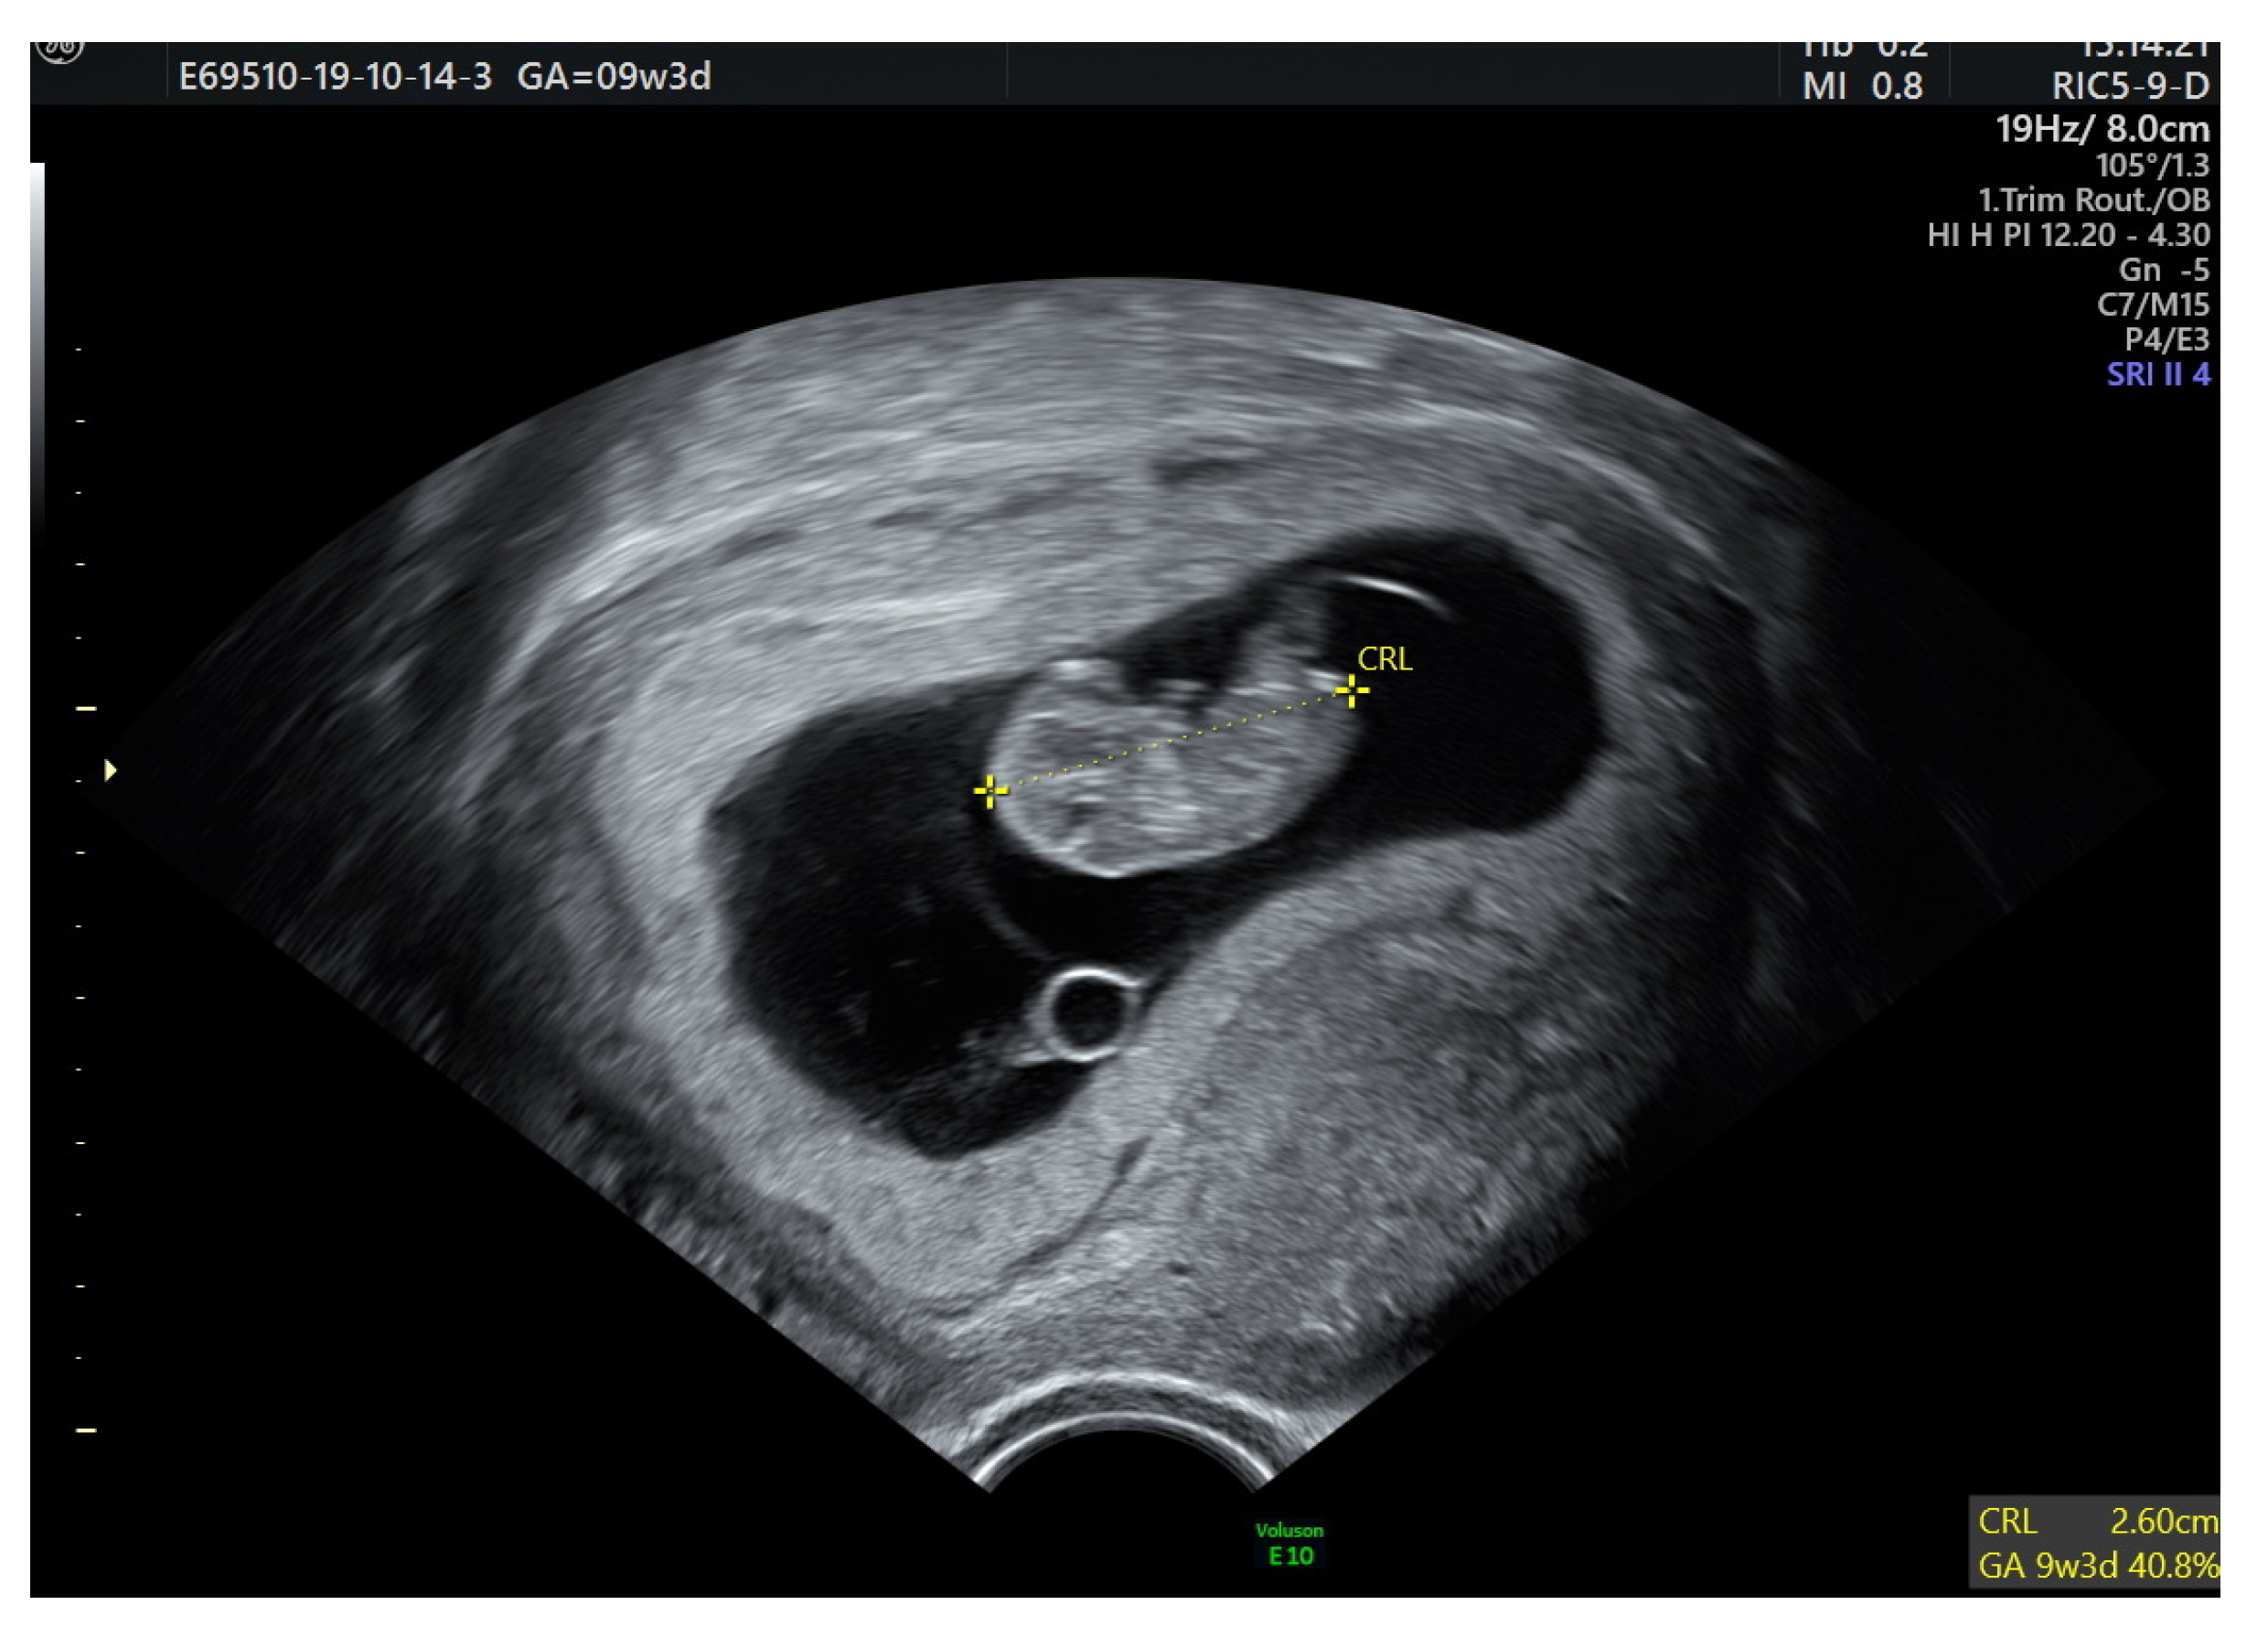

2. Case Report